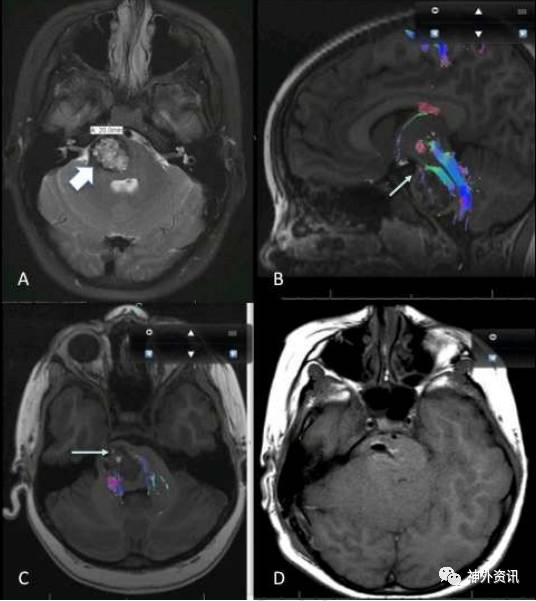

通过CM所在脑干部位的纤维束成像和彩色图,获得靶点兴趣区(ROI),对皮质脊髓束(CST)、内侧丘系(ML)、小脑下脚(ICP)、小脑中脚(MCP)和小脑上脚(SCP)进行DTI纤维束重建(图1)。DTI成像纤维束确定依据:①功能性纤维束无变形移位;②纤维束形状无中断;③功能性纤维束无中断。脑干CM手术指征:①伴有明显的神经功能障碍;②手术入路安全;③发生出血和症状恶化。对无症状、位置深在、CM较小或症状轻微的患者不考虑手术。依据CM所在部位分为三类,①中脑部CM;②桥脑部CM;③延髓部CM。采用薄层MR技术测量CM大小。确定出血事件的依据:①出现新发神经功能障碍;②CM增大;③症状加重和恶化。术后6~12周进行第一次随访检查,综合评估随访数据;使用改良的Rankin量表(mRS)计分评价预后。

图1. 中脑、桥脑、延髓以及DTI成像重建的白质纤维束解剖示意图。CST:皮质脊髓束;ML:内侧丘系;ICP:小脑脚下部;MCP:小脑脚中部;SCP:小脑脚上部。

图2. 1例桥脑CM的11岁男性患儿。A.水平位MRI显示桥脑CM(大箭头);B、C.矢状位和水平位DTI成像示重建的向前变形的皮质脊髓束(小箭头),提示前入路危险;D.术后MRI示病灶完全切除。